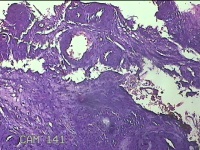

宫颈锥切物

性别

女

年龄

36岁

临床诊断

宫颈CIN2 宫颈乳头病毒感染

一般病史

检查发现CIN21个月。

标本名称

大体所见

灰白粉红色组织5.5x1.3x0.8cm一块,表面糜烂,切面灰白粉红色,质软,另有灰白粉红色组织2.3x2x0.3cm一堆,表面糜烂,切面灰白粉红色,质中。

图2